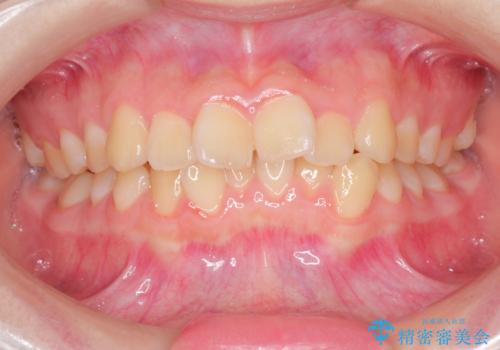

前歯のデコボコを治したい インビザラインによる矯正治療